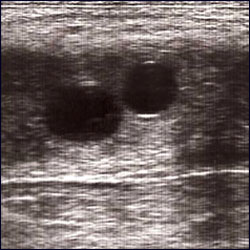

L’IA consente un migliore controllo sanitario, genetico e gestionale, soprattutto negli allevamenti sportivi. La diagnosi precoce di gravidanza avviene tramite ecografia transrettale già a partire dal 14° giorno post-ovulazione, permettendo anche l’identificazione e la gestione di eventuali gravidanze gemellari.